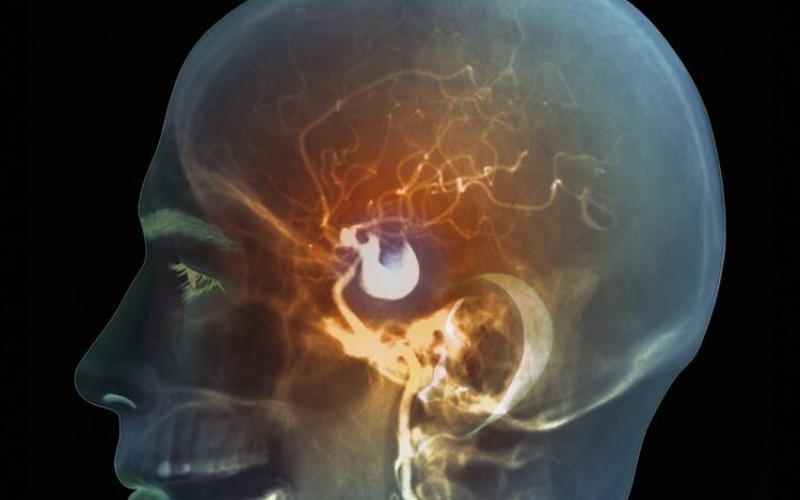

06.02.2025. | 17:37Aneurizma u mozgu je ozbiljno stanje koje ponekad može da prođe potpuno nezapaženo dok ne dođe do iznenadne, potencijalno smrtonosne rupture.

Aneurizma se javlja kada se dio zida arterije, krvnog suda, izduži i stvori izbočinu. Iako se može desiti u bilo kojem krvnom sudu, najčešće je prisutna u arterijama mozga i velikoj arteriji koja izlazi iz srca.